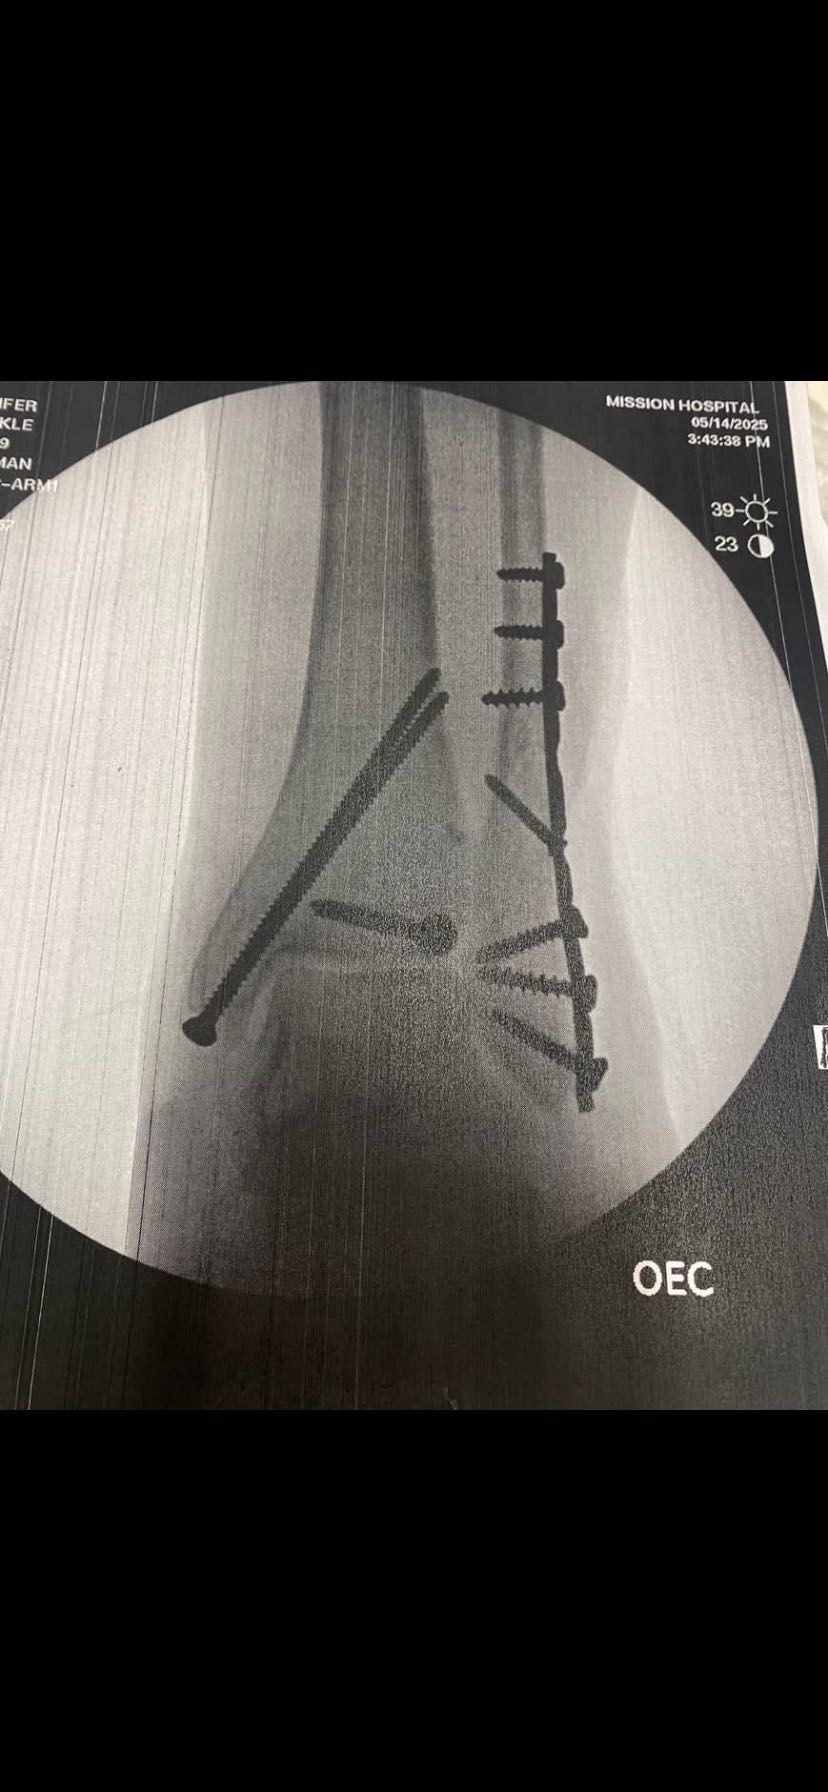

I had surgery the next morning-8 screws, two pins, and a plate. That was the easy part. The weeks after proved challenging-to say the least. I felt helpless, with only my son to help me, The pain seemed relentless. And I lost 100 percent of my independence.

The break is called trimalleolar fracture with dislocation and is in the top 7 percent of the most serious injuries one can have with an

ankle.